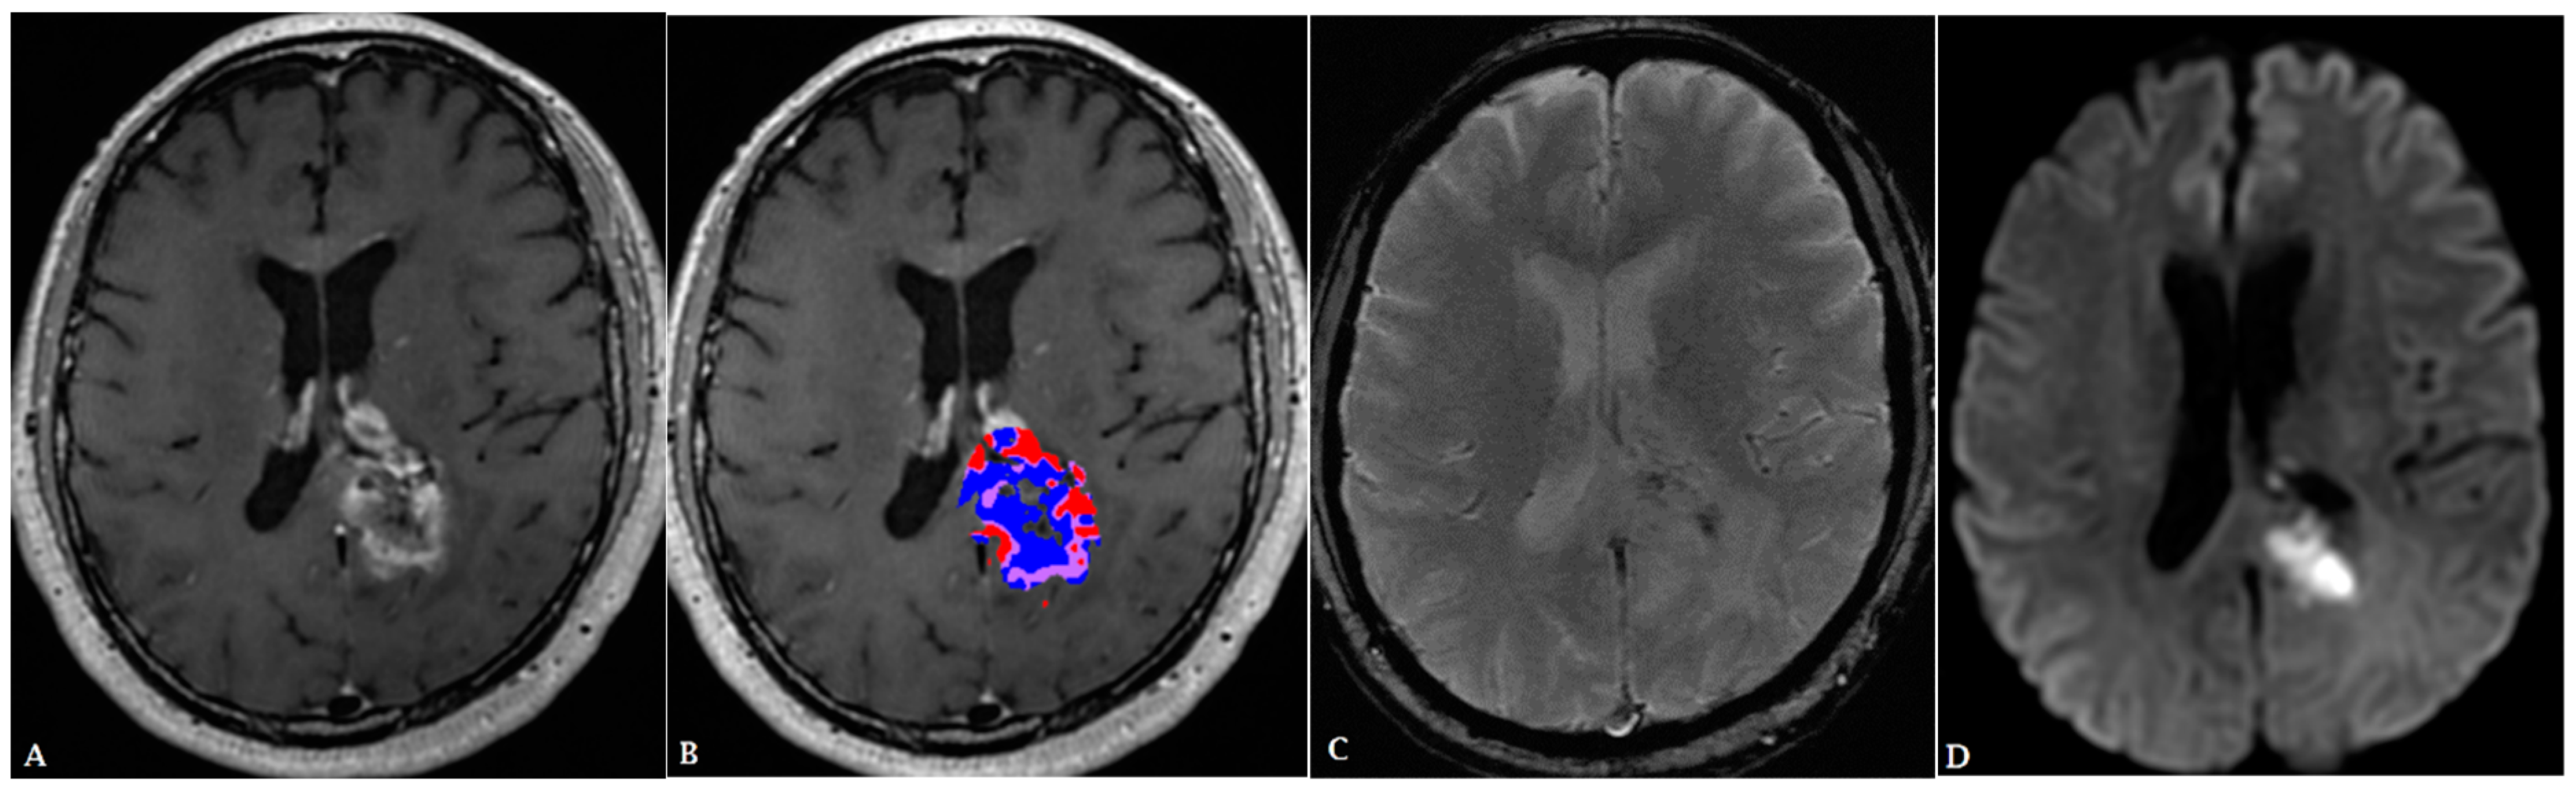

- Ismail, M.; Hill, V.; Statsevych, V.; Huang, R.; Prasanna, P.; Correa, R.; Singh, G.; Bera, K.; Beig, N.; Thawani, R.; et al. Shape Features of the Lesion Habitat to Differentiate Brain Tumor Progression from Pseudoprogression on Routine Multiparametric MRI: A Multisite Study. Am. J. Neuroradiol. 2018, 39, 2187–2193. [Google Scholar] [CrossRef] [PubMed]

- Elshafeey, N.; Kotrotsou, A.; Hassan, A.; Elshafei, N.; Hassan, I.; Ahmed, S.; Abrol, S.; Agarwal, A.; El Salek, K.; Bergamaschi, S.; et al. Multicenter study demonstrates radiomic features derived from magnetic resonance perfusion images identify pseudoprogression in glioblastoma. Nat. Commun. 2019, 10, 3170. [Google Scholar] [CrossRef] [PubMed]

- Park, J.E.; Kim, H.S.; Goh, M.J.; Kim, S.J.; Kim, J.H. Pseudoprogression in Patients with Glioblastoma: Assessment by Using Volume-weighted Voxel-based Multiparametric Clustering of MR Imaging Data in an Independent Test Set. Radiology 2015, 275, 792–802. [Google Scholar] [CrossRef] [PubMed]

- Kim, J.Y.; Park, J.E.; Jo, Y.; Shim, W.H.; Nam, S.J.; Kim, J.H.; Yoo, R.-E.; Choi, S.H.; Kim, H.S. Incorporating diffusion- and perfusion-weighted MRI into a radiomics model improves diagnostic performance for pseudoprogression in glioblastoma patients. Neuro-Oncol. 2018, 21, 404–414. [Google Scholar] [CrossRef] [PubMed]